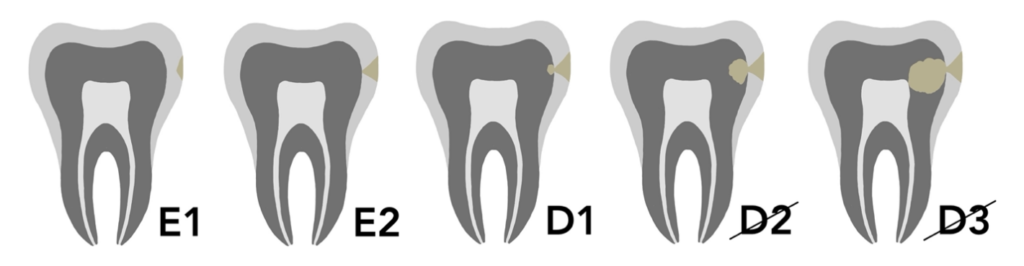

Icon Proximal – leczenie zmian próchnicowych na powierzchniach stycznych

• Wczesne zmiany próchnicowe (do granicy zewnętrznej 1/3 zębiny), wykrywane na zdjęciu skrzydłowo-zgryzowym.

• Alternatywa dla tradycyjnego leczenia wiertłem w przypadku początkowej próchnicy.

• Ochrona przed progresją próchnicy – Icon Proximal blokuje dalszy rozwój zmiany próchnicowej.